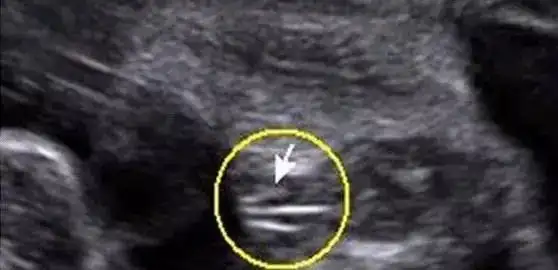

孕26周四维下睾丸的样子 如何看四维彩超识性别